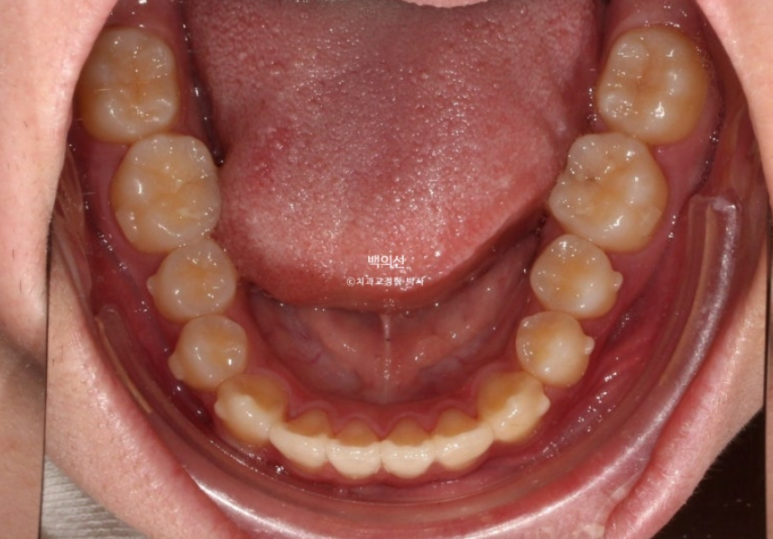

24.04

송곳니 덧니가 있고 덧니 옆 앞니는 입천장으로 나서 아랫니가 거꾸로 물리는 반대교합 입니다.

교합이 뜨는 부분들이 있습니다.

어금니 교합은 좋고 돌출이 없어서 치간삭제 소량 동반한 인비절라인 라이트 권유드렸습니다.